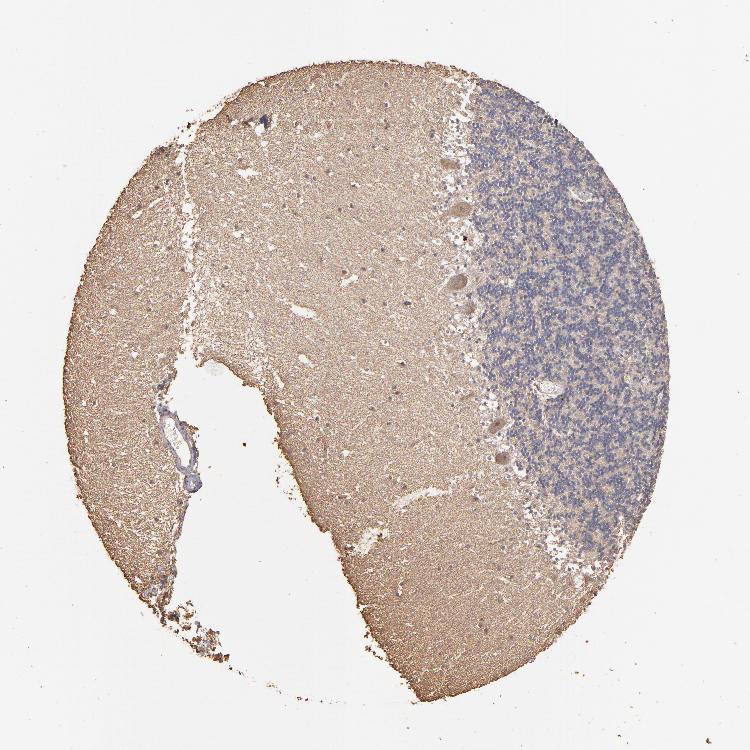

CEREBELLUM - Antibody stainingi

Antibody staining in the annotated cell types in the current human tissue is reported as not detected, low, medium, or high, based on conventional immunohistochemistry profiling in selected tissues. This score is based on the combination of the staining intensity and fraction of stained cells.

Each image is clickable and will lead to virtual microscopy that enables deeper exploration of all samples and also displays staining intensity scores, fraction scores and subcellular localization as well as patient and tissue information for each sample.

Antibody HPA002725Antibody HPA023885Antibody CAB000119

Purkinje cells MediumNot detectedNot detected

Cells in granular layer Not detectedNot detectedNot detected

Cells in molecular layer LowNot detectedNot detected